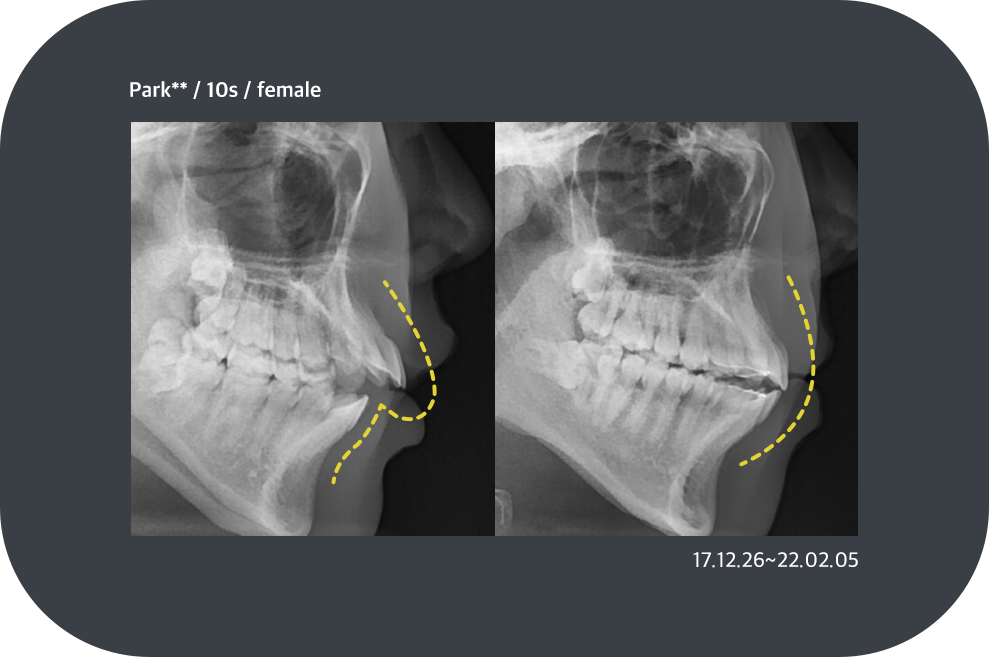

치료사례

치아교정 치료사례

ortho_case01 ortho_case01

ortho_case02 ortho_case02

ortho_case03 ortho_case03

ortho_case04 ortho_case04

*모든 증례 사진은 의료법 제23조, 제56조에 의거하여, 당사자의 동의하에 게시하였습니다.

*치료 사진은 모두 본원에서 치료한 환자분의 사진입니다.

*치료 사진은 모두 동일인의 사진이며, 동일조건에서 촬영하였습니다.

*개인의 차이에 따라 시술 및 수술 후 부작용이 발생할 수 있으며, 의료진과 충분한 상담을 받으시기 바랍니다.